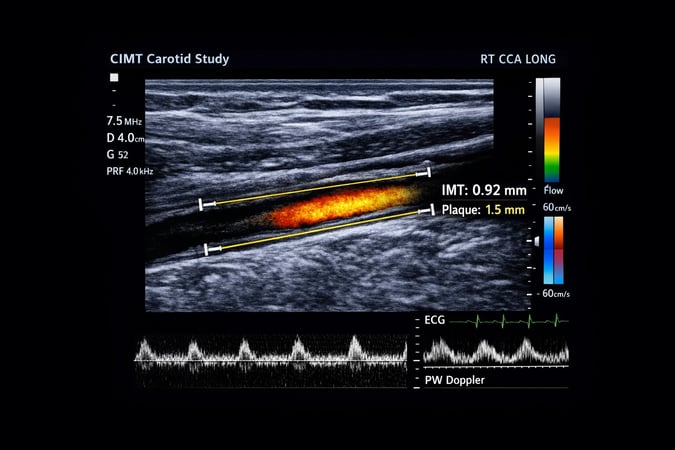

CIMT offers a rare opportunity to detect cardiovascular disease in its earliest stages, long before symptoms appear, when lifestyle intervention can meaningfully alter outcomes.² Rather than creating fear, CIMT provides clarity—shifting the conversation from crisis management to metabolic correction. A CIMT scan is a simple, non-invasive ultrasound that measures the thickness of the inner lining of the carotid arteries, the major blood vessels supplying the brain.

As metabolic stress accumulates, these arteries Walls gradually thicken and lose elasticity. Plaque may begin to form. None of this causes pain, and none of it is reliably detected by stress testing or routine cholesterol panels.³ Yet these early changes represent the same disease process that ultimately leads to heart attack, stroke, and cognitive decline.⁴

What makes CIMT so powerful is not just what it measures, but when it measures it. Numerous longitudinal studies have shown that increased carotid intima-media thickness strongly predicts future cardiovascular events, independent of traditional risk factors.⁵ In this sense, CIMT is not a diagnosis or a prediction of inevitable disease. It is an early warning system—and for those willing to act, a valuable opportunity.